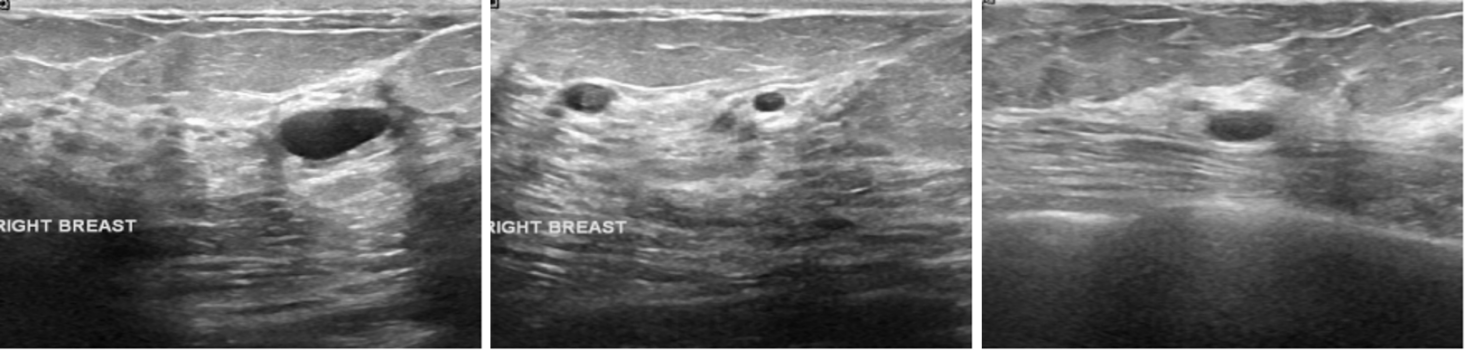

The experimental data for this study was sourced from the Breast Ultrasound Images Dataset on the Kaggle platform. This open-source dataset comprises 780 breast ultrasound images collected in 2018 from 600 female patients aged 25 to 75. The images are in PNG format with an average size of 500×500 pixels and include ground truth labels categorised into three classes: normal, benign, and malignant. For binary classification, this study categorises the images into two groups: "non-diseased" (normal) and "diseased" (benign + malignant) ( Figure 2,3).